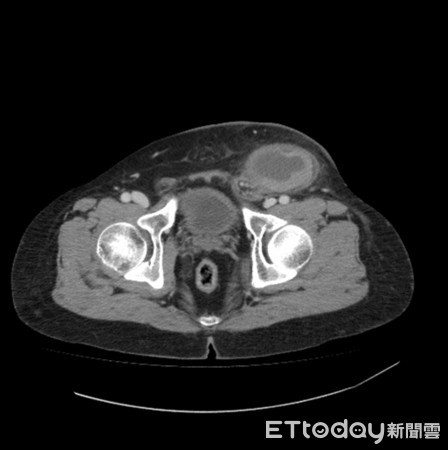

Tinh hoàn bé trai nằm lạc trong ổ bụng

TP HCM - Bé trai 2 tuổi, ở Bến Tre, gần đây bố mẹ sờ không thấy tinh hoàn ở bìu nên đưa đến khám tại Bệnh viện Nhi đồng 2.